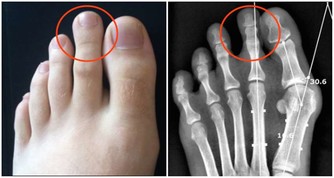

胃:怕冷 胃、十二指腸潰瘍發病有季節性,秋冬和冬春交替都是高發期,寒冷的天氣尤其要注意養胃。胃痛、腹部不適,消化能力降低,這時進食生冷食物就會引起或加重胃部不舒服的症狀。 心:怕咸 食鹽過度會給身體帶來高血壓、心血管疾病等隱患。鹽中含有大量的鈉離子,鈉會引起體內血容量的增加,所以食用過多的鹽,就會導致血壓升高,心臟負擔也會加重。 肺:怕煙 除了吸煙、被動吸煙外,廚房油煙、裝修污染等室內環境污染,也是引發肺癌的危險因素。研究表明,廚房通風不良相比通風良好者,患肺癌風險增加了49%。 腎:怕肉